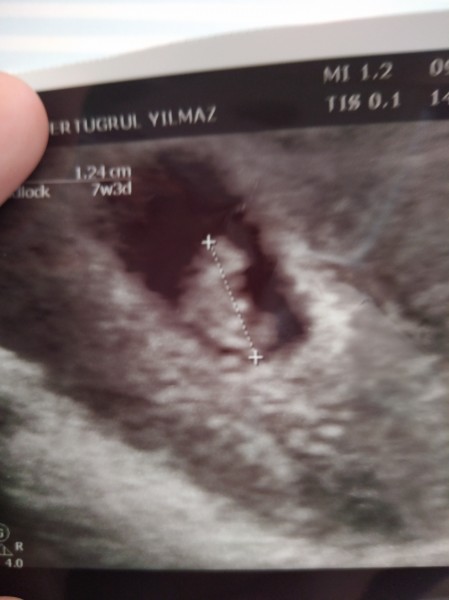

Kalp atışlarını bir türlü görmemiştik sonunda duyduk

Gebelik haftası 7+5

1cm 24ml

Ben bundan 12gün önce gittim o zmn 5+5 dedi kese 9mlm Di şimdi bilmiyorum bebek 1cm,24ml